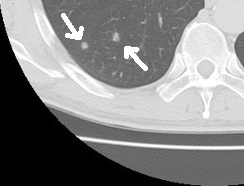

これにより、レントゲンでは重なって見えなかった肺の内部を、1ミリ以下の厚さで細かく観察することが可能になります。

前後の重なりがないため、心臓の裏側も、横隔膜の陰も、まるで見透かすように確認することができるのです。

微細な変化を逃さない

CTの最大の武器は、その圧倒的な「解像度」です。

レントゲンでは判別できないような5ミリ以下の小さな影も、CTならくっきりと写し出します。

これにより、肺がんの早期発見はもちろんのこと、肺炎の種類(細菌性なのか、ウイルス性なのか、あるいは免疫の異常によるものなのかなど)を推測する大きな手がかりになります。

死角ゼロの安心感

「平面」ではなく「立体」で捉えるため、肺の隅々まで死角がありません。

また、レントゲンでは重なって見えがちな肺の表面近くにできた小さな異常や、血管に沿って広がる細かな炎症なども、それぞれしっかりと分かれて見ることができます。